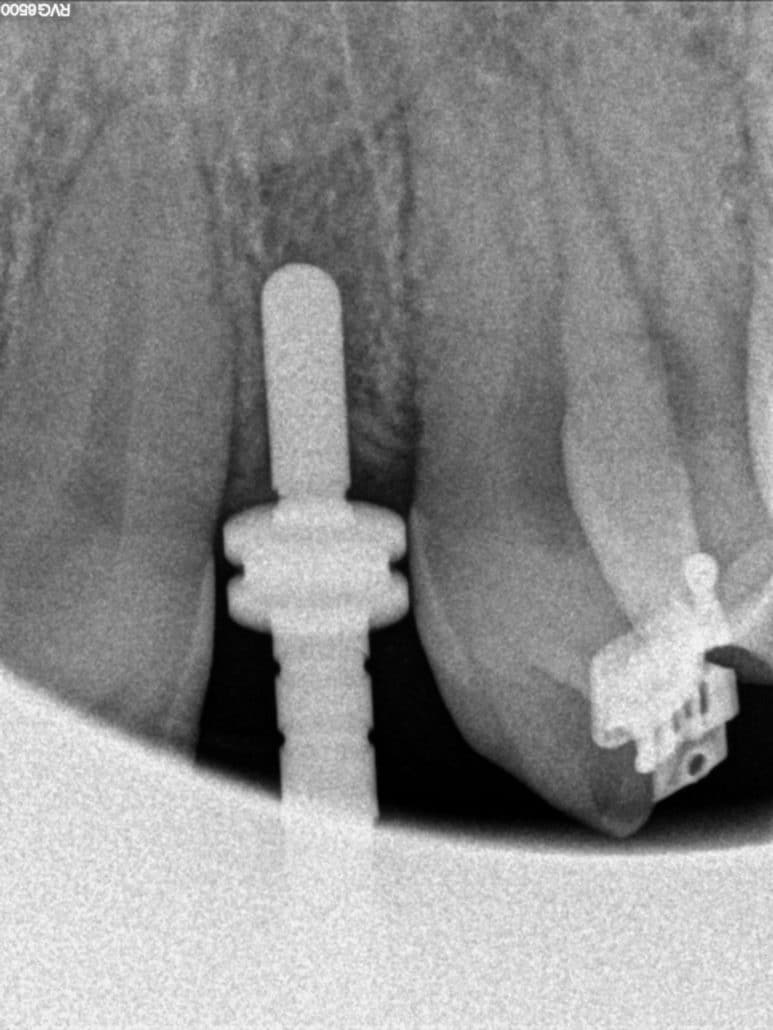

Este ejemplo muestra la colocación de un implante complejo en el sector anterior con poco espacio entre las raíces de los dientes adyacentes. Cualquier desvío en la colocación de un implante puede resultar crítico en su colocación por ello mostramos este ejemplo de un implante correctamente colocado en un espacio estrecho: